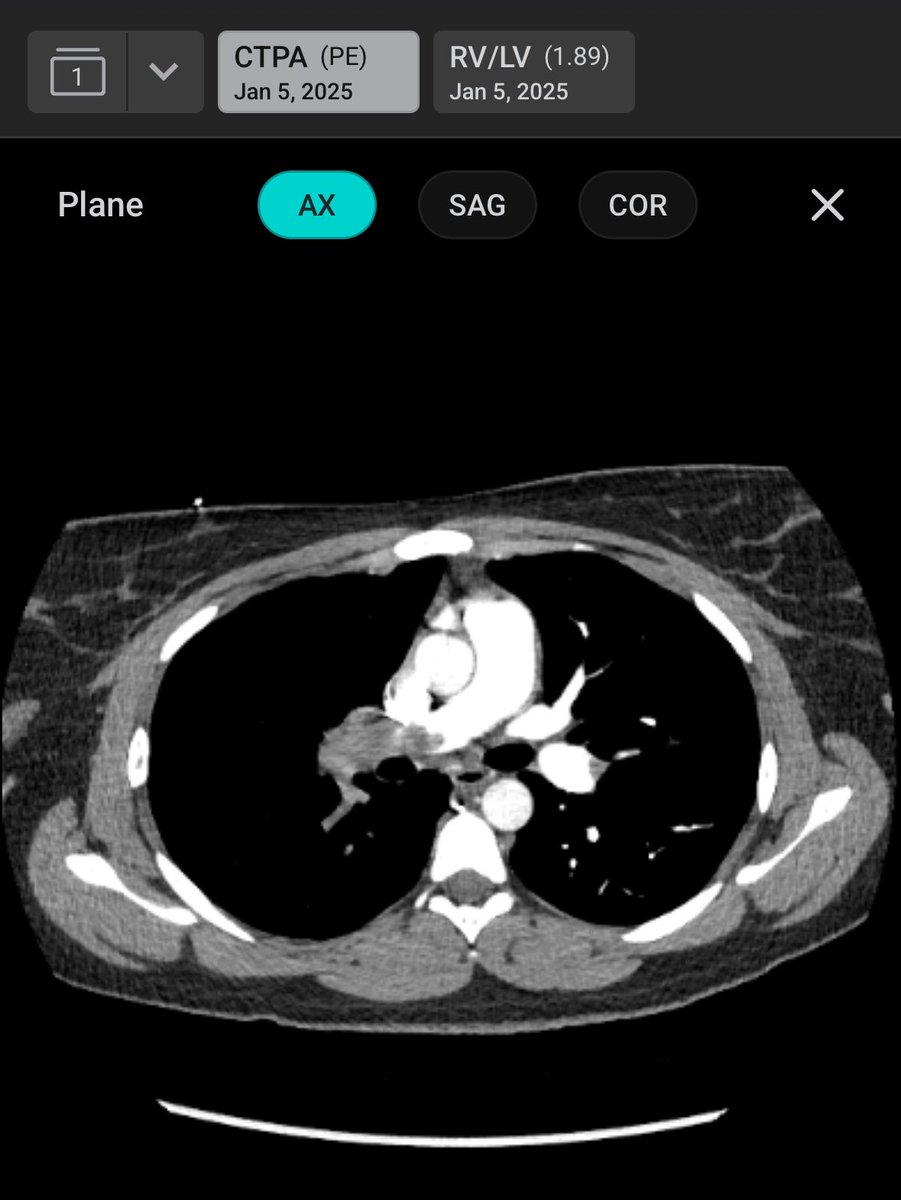

We’re excited to share enrollment for HI-PEITHO is now complete! With 544 patients enrolled across 72 sites in the United States in Europe, this landmark trial compares EKOS (Ultrasound Assisted Thrombolysis) with Anticoagulation vs Anticoagulation Alone in the treatment of intermediate-high risk PE patients. The study was a collaboration between The PERT Consortium, University Medical Center Mainz, and Boston Scientific. We extend our congratulations to all investigators and enrollment sites involved in this one-of-a-kind trial that will inform strategies for PE treatment around the world.#pe #pulmonaryembolism #hipeitho @bostonsci @bsc_pi